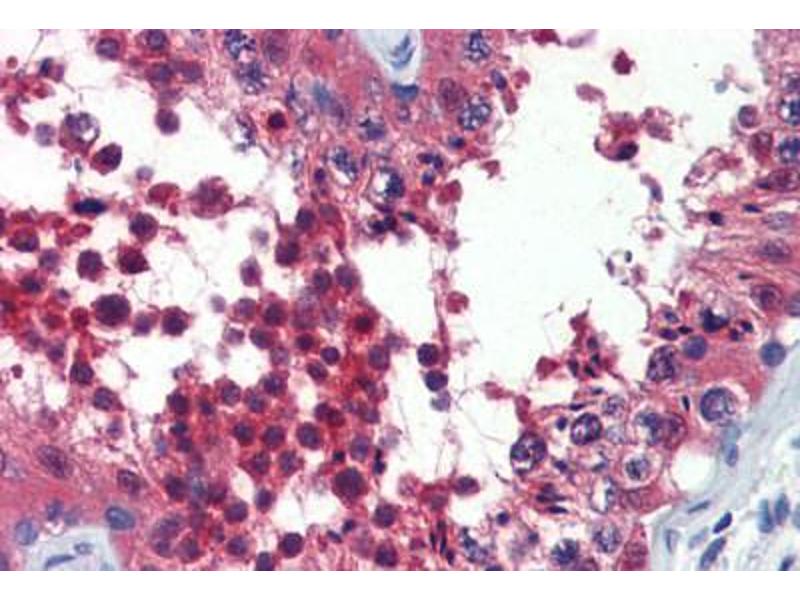

Usage: Immunohistochemistry: This antibody was validated for use in immunohistochemistry on a panel of 21 formalin-fixed, paraffin-embedded (FFPE) human tissues after heat induced antigen retrieval in pH 6.0 citrate buffer. After incubation with the primary antibody, slides were incubated with biotinylated secondary antibody, followed by alkaline phosphatase-streptavidin and chromogen. The stained slides were evaluated by a pathologist to confirm staining specificity. The optimal working concentration for this antibody was determined to be 10 μg/mL -